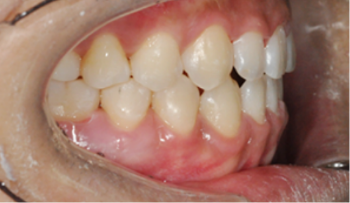

성장기 아동의 교정 치료

영구 치열의 교정 치료

수술을 위한 교정 치료